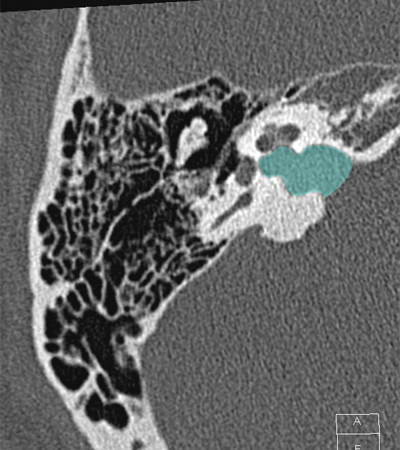

Cochlea Internal auditory canal Vestibule Posterior semicircular canal Head of malleus Body of incus Incudomallear joint

Radioanatomy of Temporal bone